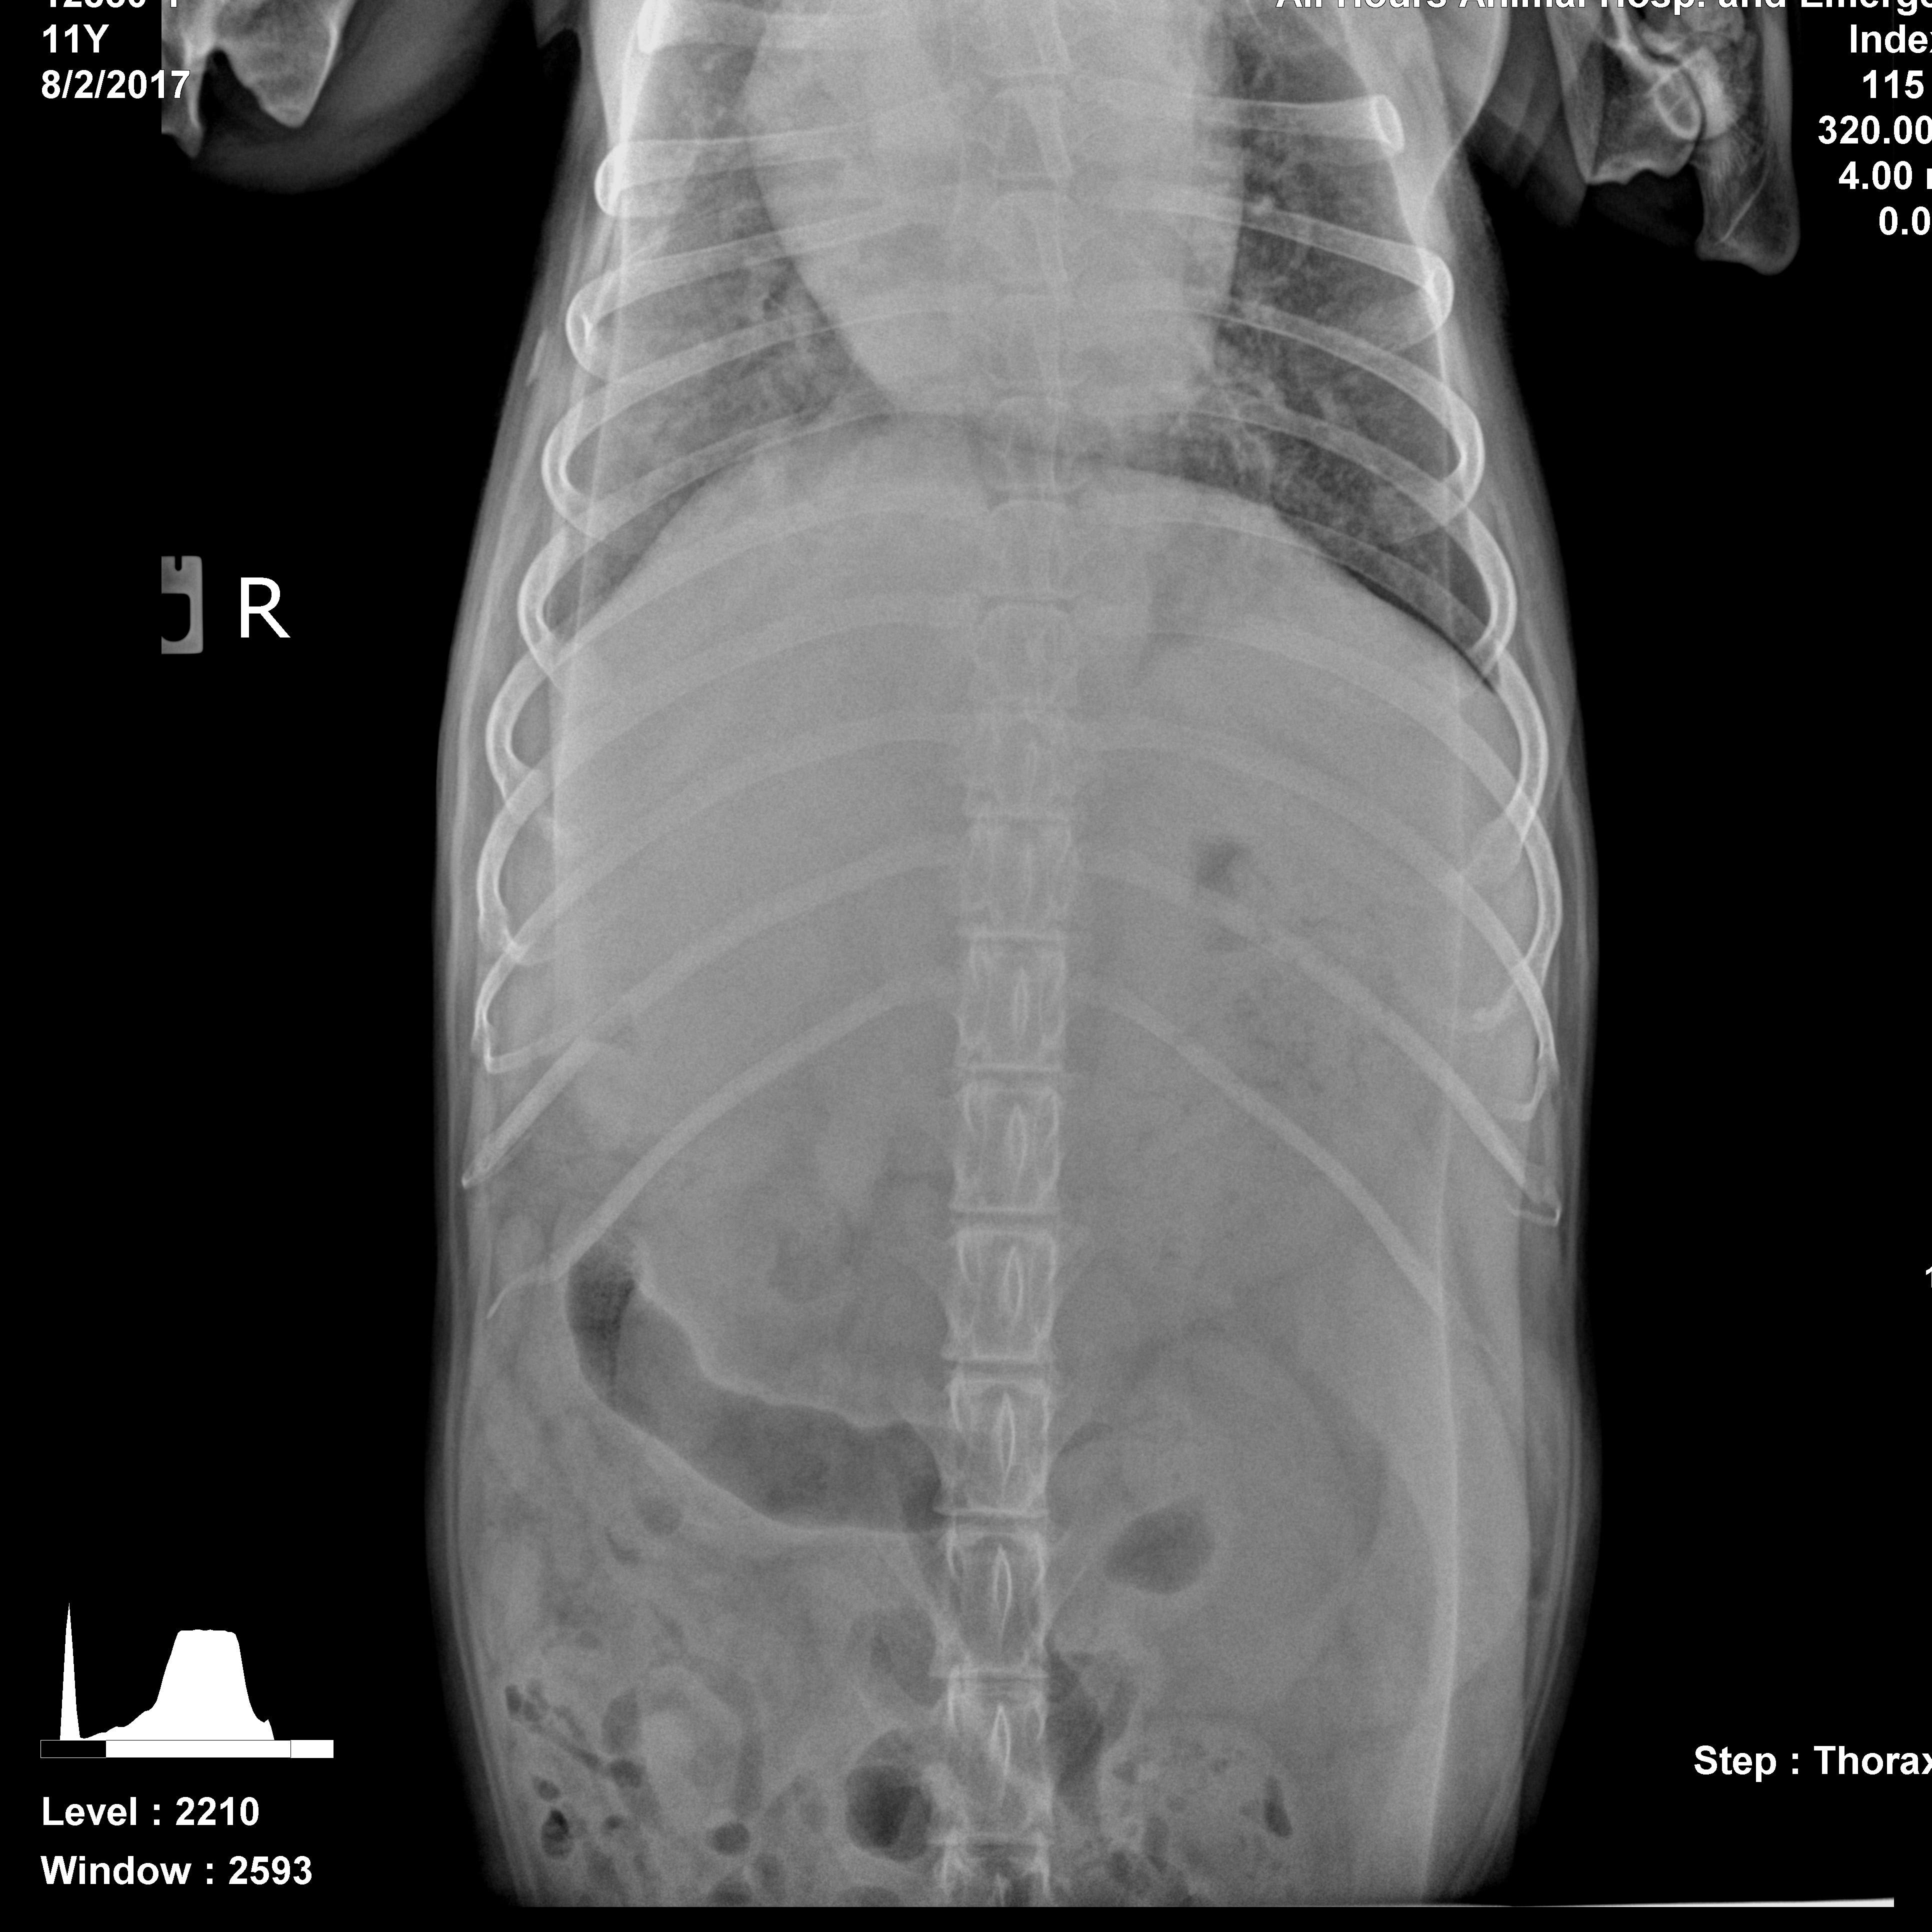

My dog (11 year old Golden Retriever) was very lethargic, not eating, breathing heavy, and weak on her legs about a month ago. I took her in to 24 hour vet and they did x-rays and blood work. Her platelets were at 7. Based on x-rays, the vet concluded that she has a spleen tumor and put her on prednisone. The vet gave her 5 to 6 months. I haven't take her in to regular vet because they are always booked week in advance. Just wanted to get second opinion based on photos provided. Thanks.

It can be very difficult to evaluate x-rays without being on the computer that took them - I can't manipulate the lightness and darkness or zoom in all the way. That being said, I am concerned that there is something very serious going on in Jasmine's liver. It is much, much larger than in a normal dog. I can't see the entire spleen, but the parts that I see appear normal. I can also see that there is some free fluid in her chest cavity - this would be fluid between the lungs and chest wall that can cause trouble breathing. I would recommend re-evaluation immediately with an emergency vet. There could be many things going on, but the heavy breathing you described combined with the abnormalities in the chest have me worried that she may be having severe issues with breathing. This can cause severe anxiety and stress in a dog. The vet will probably want to repeat the x-rays and bloodwork, and may be able to draw off fluid if it is still there to ease her breathing.